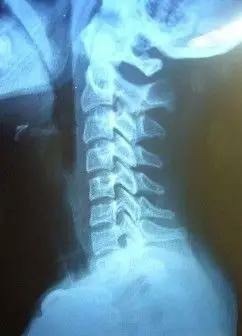

对于现如今的人来说,颈椎部位出现问题的特别多,尤其是长期坐班的群体。而当他们的颈椎出现病变之时,一般都会伴随精神萎靡和注意力不集中的症状,进而就会对他们的工作和生活造成一定的影响,而颈椎病就是这类疾病中的一种。那么下边就随小编一起来看看颈椎病都有哪些问题呢?

颈椎的生理曲度还能够恢复吗?1、年轻人容易获得较大程度的恢复当年轻人出现颈椎生理曲度的变直或者反弓的时候,此时颈椎部位的肌肉和关节柔韧性较好,可以通过一些治疗手段、康复锻炼或者调整睡觉时枕头的高度等,在最大程度上恢复颈椎的生理曲度。2、老年人则很难恢复颈椎的生理曲度对于中老年人来说,由于颈椎的退化,颈部关节肌肉的衰老,很难再恢复颈椎原有的生理曲度。此时如果过度追求恢复生理曲度还有可能导致颈椎病的症状,因此不建议强行恢复颈椎的生理曲度。所以,在发现颈椎生理曲度变化时应尽早干预。

颈椎病的症状都有哪些呢?1、脑动脉硬化或小脑疾患由于颈椎增生性改变压迫椎动脉引起基底动脉供血障碍,导致一时性脑供血不足,患者会在行走中因突然扭头、身体失去支持而摔倒,并伴有剧烈眩晕或头痛、恶心、呕吐、出汗等症状。但和脑动脉硬化不同,颈椎病患者发病跌倒后,会因颈部位置改变而很快清醒并站起,不伴昏迷,亦无后遗症。2、心绞痛或心律不齐颈背神经根受颈椎骨刺的刺激和压迫,会引发心前区疼痛、胸闷、气短等心绞痛症状以及心动过速或过缓。当患者的颈部症状不明显而心血管症状较重时,往往被误诊。和冠心病不同的是,颈椎病患者的疑似心绞痛症状多在低头工作过久、突然的扭头或甩头后发生,患者还会自觉颈部活动受限、颈椎伴有压痛。3、视力障碍 这种情况是由于颈椎病造成的植物神经功能障碍。具体表现为患者的视力下降、间歇性视力模糊、一只眼或双眼胀痛、怕光、流泪、视野缩小等,有时还伴随着颈部疼痛。4、高血压有些高血压是由颈椎病引发,也就是颈性高血压。当中下段颈椎错位时,刺激了颈动脉窦,使血压突然升高(如起床时、低头时),有时却又降到低于正常血压值。颈性高血压患者无血管、心、脑和肾等器质性病变,使用降压药物治疗无效,并且常常伴有颈部疼痛、上肢麻木等现象。5、 视力下降颈椎病还可表现为视力下降、间歇性视力模糊、一眼或双眼胀痛、怕光、流泪、视野缩小,甚至出现视野缩小和视力锐减,个别患者还可发生失明,但多数伴有颈椎病的其他症状,如颈肩疼痛、颈部活动受限等。